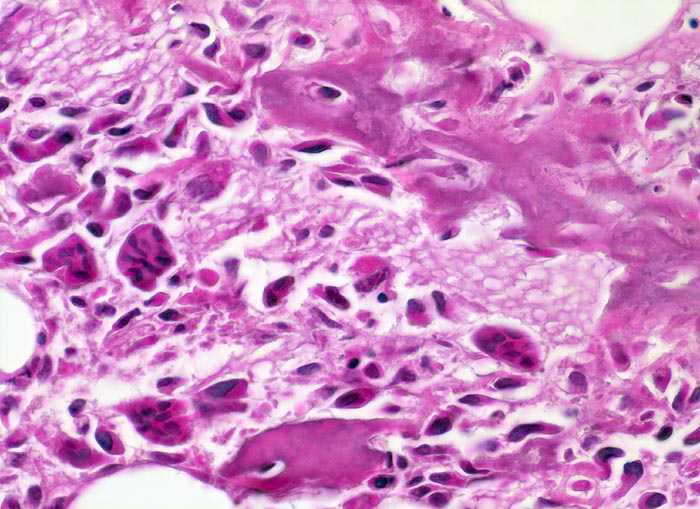

Morphologische Merkmale:

• Tibiametaphyse mit angrenzendem Weichteilgewebe.

• Das Sarkom infiltriert diffus den spongiösen Knochen der Diaphyse und hat präexistente Knochenbälkchen verdrängt.

• Der Tumor hat die Korticalis destruiert und infiltriert die angrenzende Skelettmuskulatur.

• Der Tumor besteht aus neugebildetem bereits verkalktem Knochen oder einem Netzwerk von primitiven Osteoidtrabekeln. Entlang oder innerhalb der Osteoidtrabekel lokalisierte polymorphe Tumorzellen mit ausgeprägten Kernatypien und zahlreichen Mitosen. Leicht verwaschene Kernstrukturen als Folge der Gewebsentkalkung.